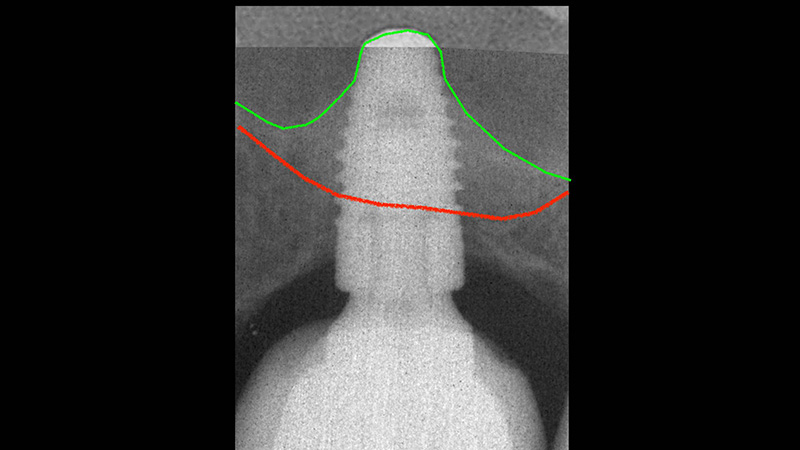

En rouge : la situation initiale.

En vert : le niveau osseux obtenu 3 ans après la pose de l’implant.

CBCT avant et après la pose combinée au comblement et à l’élévation du plancher sinusien.

Évolution radiologique d’un environnement osseux péri-implantaire après un protocole d’extraction puis implantation.

Évolution radiologique d’un environnement osseux péri-implantaire après un protocole d’extraction, puis implantation/comblement sinusien. Notez le gain osseux après seulement 6 mois.

Pose d’un implant de 7 mm, puis évolution de l’os périmplantaire apicale au fil des années.

10 ans après, notez l’aspect radiologique de la corticale péri-implantaire.